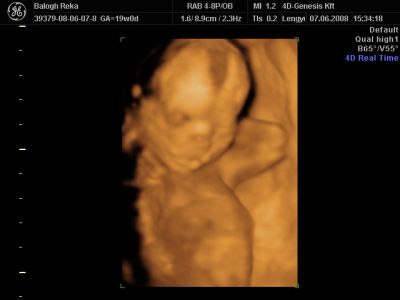

Huhh, hát annyira jó élmény volt, most tök boldog vagyok! Nagyon örülök, hogy mégis elmentem mégegyszer, mert sokat vacilláltam ám. A 4D Genesis egyszerűen szuper, mindenkinek nagyon nagyon tudom ajánlani, ezen belül is engem a Lengyel Györgyné Márti fogadott. Szuper ez a nő, akkora átéléssel és profizmussal csinálta az egész vizsgálatot! Mindent részletesen megnézett, megmutatott, elmagyarázott, nem sajnálta az időt. A felvétel gyönyörű lett, az egész baby nagyon szépen látszik, végig fent volt és mocorgott, hihetetlen aranyos volt, és nagyon szép!

Bemutatott párszor, ezek mind meg is vannak örökítve!

Na és a lényeg...jöjjenek a sztárfotók! Bocsi előre, 8 lesz és kicsit nagyok, de nem tudtam választani, azokat a bemutatásokat mind muszáj volt felraknom, tök vicces!